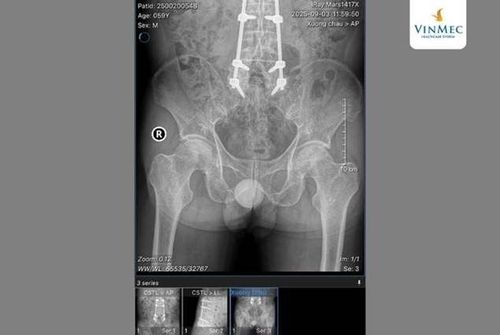

Tới Bệnh viện Đa khoa Vinmec Hải Phòng, bệnh nhân được tham khám và tư vấn trực tiếp với TS.BS Nguyễn Hữu Mạnh - Giám đốc Bệnh viện Đa khoa Vinmec Hải Phòng. Tại đây, sau khi thăm khám và đánh giá phim MRI và X - quang, bác sĩ chẩn đoán bệnh nhân bị hoại tử chỏm xương đùi mức độ nặng - tình trạng mà phần chỏm xương mất hoàn toàn chức năng, không thể hồi phục bằng các phương pháp bảo tồn. Bệnh nhân được các bác sĩ chuyên khoa chỉ định phẫu thuật thay khớp háng toàn phần để lấy lại khả năng vận động.

Sau khi được hội chẩn kỹ lưỡng, bệnh nhân được chỉ định thay toàn bộ khớp háng nhân tạo. Ca phẫu thuật diễn ra thuận lợi và chỉ sau vỏn vẹn 12 giờ, bệnh nhân đã có thể tập đứng, tập đi lại dưới sự hướng dẫn của đội ngũ vật lý trị liệu.